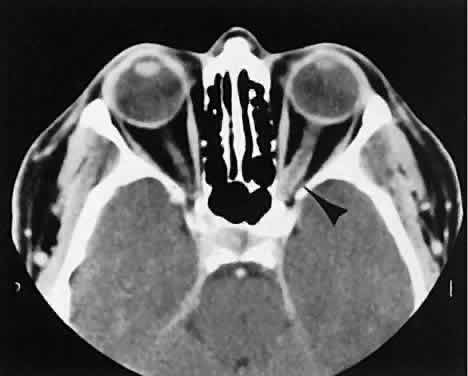

The vascular tumors under consideration are capillary hemangioma, cavernous hemangioma, lymphangioma, and hemangiopericytoma. Capillary hem-angiomas and lymphangiomas are benign infiltrativetumors seen in a pediatric population. Capillary hemangiomas have a homogeneous consistency, display intense uniform contrast enhancement, and do not usually displace any orbital structures (Fig. 12). Phleboliths are a characteristic finding in hemangiomas and, when present, are virtually pathognomonic of this diagnosis.56

Fig. 12. A. Axial view shows an exuberant homogenous soft-tissue mass infiltrating the retrobulbar space and periorbital tissue, typical of large infantile capillary hemangioma. B. Extension (arrow) into the adjacent periorbital tissues can be seen on the coronal view.